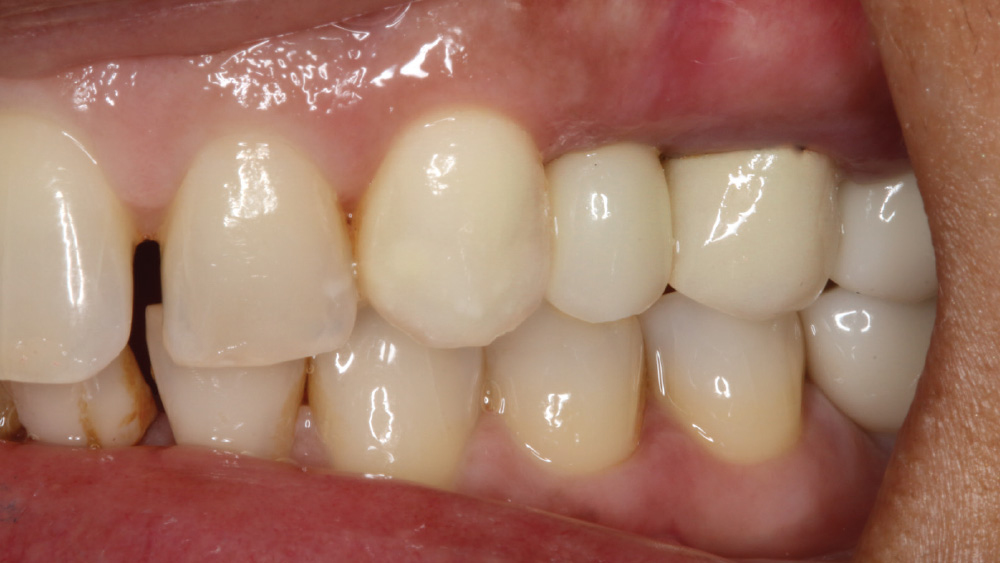

CASE REPORT

The following case, which I performed alongside Dr. Stephanie Tilley of Pensacola, Florida, illustrates the use of both surgical techniques for the same patient, who presented with edentulous spaces in the areas of both right and left maxillary first bicuspids. Due to varying soft-tissue volume on each side of the arch, implant surgery was performed using a flapless procedure for one site, while the attached gingiva was reflected to expose the available hard tissue for the other. As a result of proper site evaluation, treatment planning and restorative-driven implant placement, both surgical techniques led to successful outcomes for the patient.